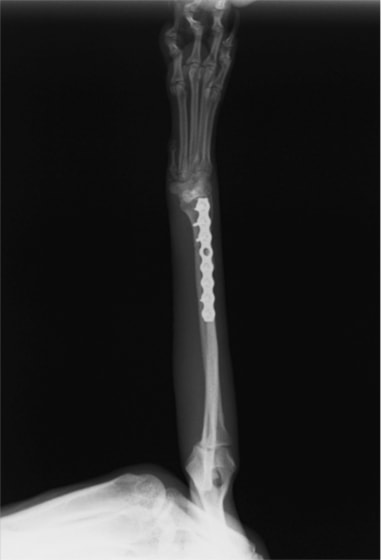

トイプードル 右遠位橈尺骨短斜骨折のALPSによる内固定

Locking Compression Plate

LCPは、スクリュー(ネジ)とプレート(金属の板)をロックする特殊な構造により骨折部位を固定する新しい世代のプレートシステムです。ひとつのホールでロッキングスクリューとスタンダードスクリューの使用を選択できるユニークな構造をしているため、骨折断端間の圧迫を目的とした従来型プレート固定法に加え、高い角度安定性を有するロッキングスクリューを用いた固定法の選択が可能です。従来のプレートシステムでは困難だった部分の骨折や癒合不全の症例に高い治療効果をもたらします。

当院ではAdvanced Locking plate system(ALPS)と、Locking compression plate system(LCPS)という骨接合法で骨折症例の治療を行っています。